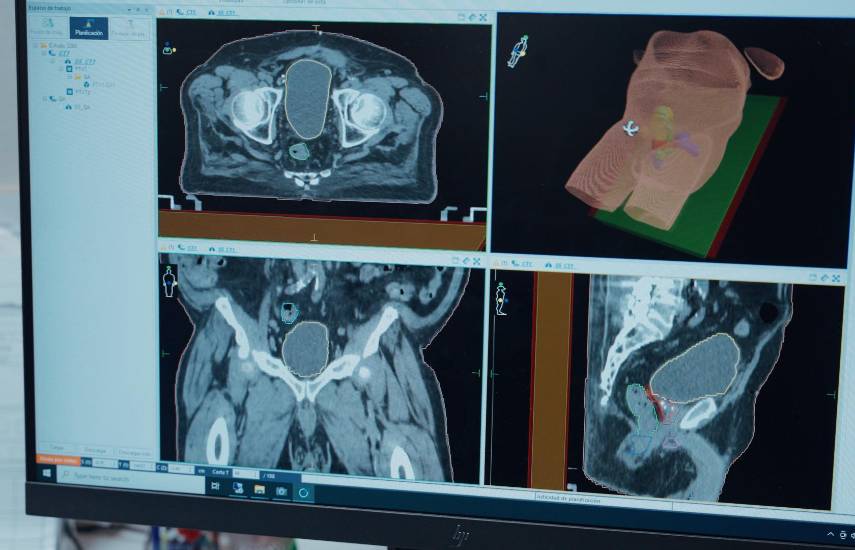

Los pacientes beneficiados hasta el momento padecen, en su mayoría de cáncer de mama y próstata, los de mayor incidencia en el país. El Centro ofrece tratamientos más precisos y seguros para los pacientes con tres aceleradores lineales de última generación en el Servicio de Radio-Oncología.

“Estos equipos nos permiten brindar tratamientos con precisión milimétrica, reduciendo los tiempos de espera y mejorando la calidad de vida de nuestros pacientes”, destacó el Dr. Gaspar Pérez Jiménez, médico radio-oncólogo y jefe del Servicio de Radio-Oncología del ION.

Con estos nuevos aceleradores lineales se brindan tratamientos con intensidad modulada, una tecnología que se ajusta a la forma del tumor y protege el tejido sano, logrando resultados más eficaces y con menos efectos secundarios.

Además, el Centro cuenta con un cuarto acelerador lineal, ligado a un resonador magnético, que aplica una tecnología de radioterapia adaptativa que solo poseen alrededor de 100 hospitales en el mundo. Esto convierte a Panamá en el segundo país de Latinoamérica, después de México, en contar con este innovador equipo, que se e|spera entre en funcionamiento en el año 2026.